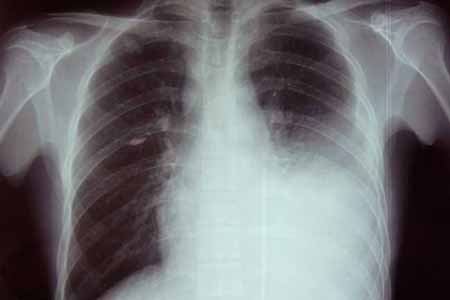

4、引发呼吸道疾病:多见胸膜炎和间质性肺炎,特别是长期患病的老年人。